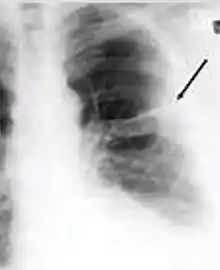

4. Pleural effusion - Presence of a significant amount of fluid within the pleural space. This finding must be distinguished from blunting of the costophrenic angle, which may or may not represent a small amount of fluid within the pleural space (except in children when even minor blunting must be considered a finding that can suggest active TB).

Chest x-ray showing dense opacity pleural effusion in the lower left lung of primary pulmonary TB.